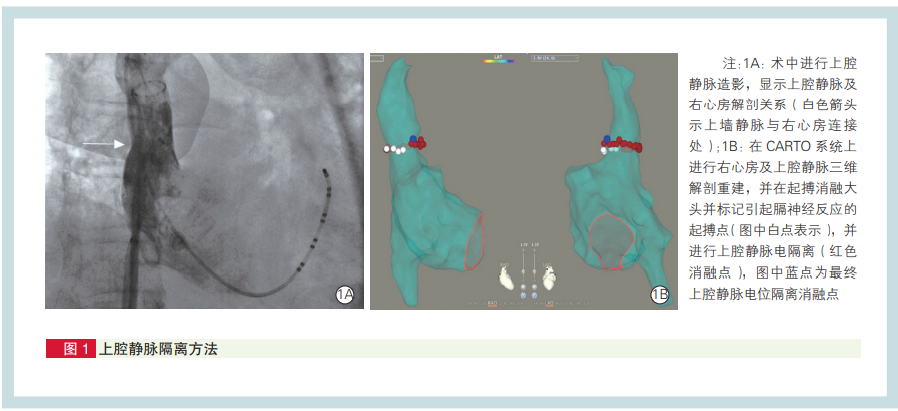

常规用右前斜(RAO)30°行上腔静脉造影,显示上腔静脉及右心房连接处(图 1A)。运用PentaRay电极导管进行右心房及上腔静脉三维重建,用PentaRay电极导管或 lasso 电极记录上腔静脉电位。用 SmartTouch 压力监测消融导管送至上腔静脉及右心房连接处上1~2 cm 部位进行起搏(电压 15 mV,脉宽 2 mV),将能引起膈肌刺激的起搏点在三维模型上进行标注(图 1B)。用 SmartTouch 压力监测消融导管送至上腔静脉及右心房连接处上 1~2 cm,在相同水平面并避开膈神经标记部位进行消融,消融预设能量 20~25 W、预设温度 43℃,压力控制在 10~15g 之间,生理盐水灌注 速度在消融时为 17 ml/min、消融间歇 2 ml/min,直至上腔静脉电隔离。本组阵发性房颤患者 50 例患者常规进行肺静脉隔离后,继续行上腔静脉隔离。49 例患者均在未消融到引起膈肌刺激部位时已成功隔离上腔静脉电位,仅一例患者需消融术中标记到的膈肌刺激部位而放弃上腔静脉电隔离,术中及围术期无一例出现膈神经麻痹及窦房结损伤。术后随访 12 个月,未发现患者出现膈神经损伤及窦房结损伤相关症状。该上腔静脉隔离方法不必进行上腔静脉消融同时进行膈神经起搏,消融中只要避开膈神经 反应部位即可,并且上腔静脉隔离率高且随访无并发症发生。来源:李希,张劲林,唐成,等. 心房颤动上腔静脉节段性电隔离方法及安全性评估. 中国循环杂志, 2021,36:39-42. DOI:10.3969/j.issn.1000-3614.2021.01.007.